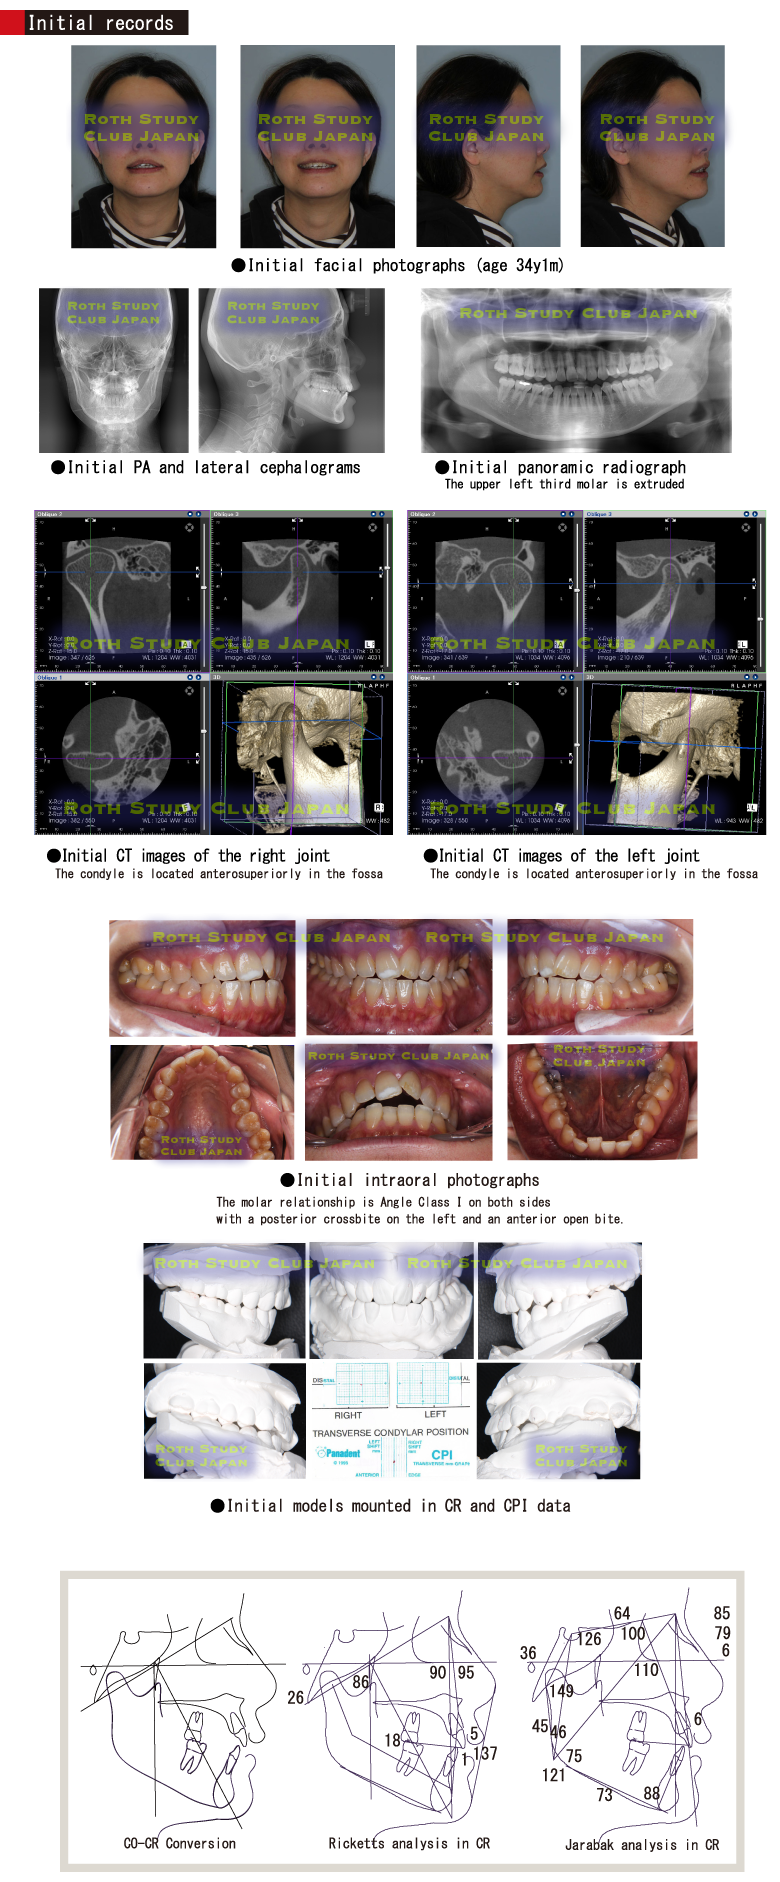

Initial records